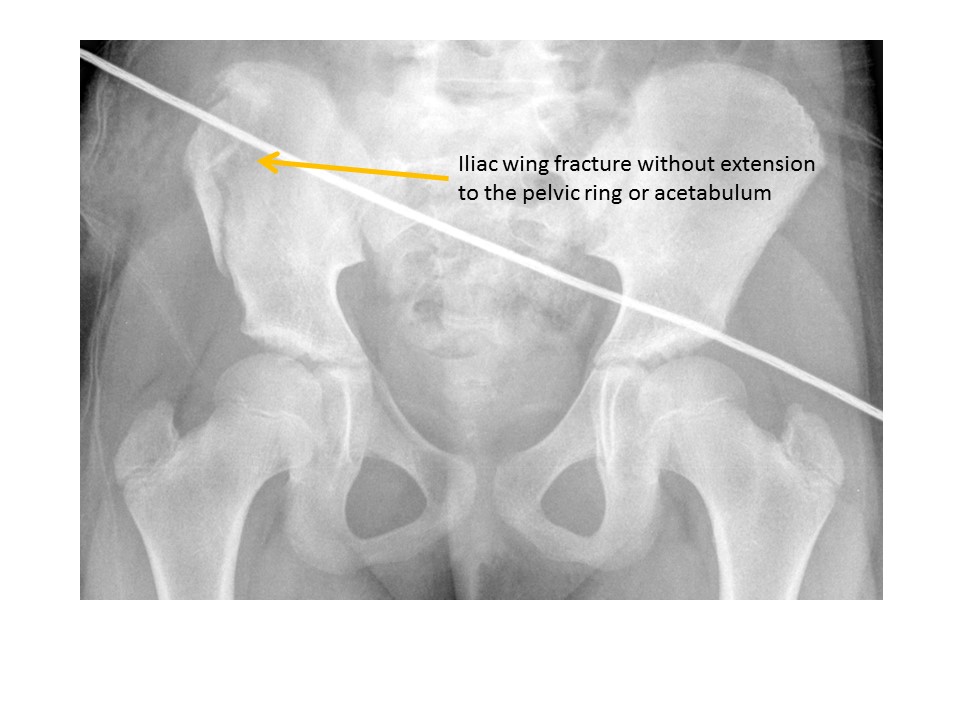

Iliac wing fractures are present. [Yes/No]

Posterior iliac bone fractures are present. [Yes/No]

Iliac crest avulsion fractures are present. [Yes/No]